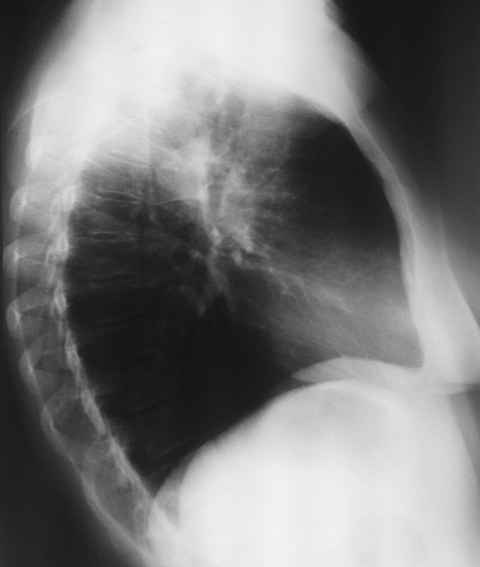

Женщина 32 года; месяц как кашляет. Повышения температутры тела не отмечала. Изначально выполнили рентгенографию. Что делать дальше?

Ок, мы определились с дифференциальным рядом при такой рентгенологической картине (Затемнение верхених сегментов правого лёгкого, S2). Какую рекоммендацию Вы бы дали такому пациенту? Что будем делать дальше?

Далее рекомендуем лабораторные исследования, КТ легких.

Консультация фтизиатра (инфильтративный туберкулез? пневмония?)

Давайте определимся, для начала обозначим какие КТ признаки мы видим на представленных сканах. И главное это не перечисление вариантов диагнозов (если нет однозначного варианта); а определить что надо сделать следующим этапом для достижения окончательного диагноза.

Вполне адекватная тактика. КТ контроль через 3-4 недели после антибактериальной терапии, совершенно правильно.

В данном случае, пульмонолог решил пойти на бронхоскопию; был забор материала. Лабараторный анализ (ПЦР) выявил положительную реакцию на туберкулёз.